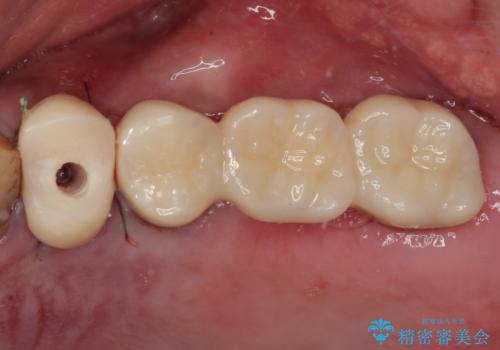

- 土台の歯が割れてしまって、歯がグラグラしているとのことで来院された患者様です。

いずれの歯も抜歯が必要な状態であり、抜歯即時埋入によるインプラント治療を行うこととしました。

右上奥歯は骨欠損の範囲が広いため、抜歯即時埋入は可能であっても、即日で仮歯を装着する即時荷重は難しいと判断されたため、手前の歯まで仮歯を装着することとしました。

強い咬合力により歯根破折を繰り返しているため、即日荷重あるいは早期荷重による他の歯への負担を軽減することが重要となります。

抜歯即時埋入インプラントは、咬合力によるトラブルを回避する、非常に有用な手段となります。